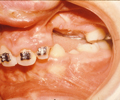

En el supuesto de que la fisura de la encía no se hubiera cerrado quirúrgicamente en el primer año de vida (gingivoperiostioplastia), se realizará entre los 7 y 11 años, previo tratamiento ortodóncico, y mediante la colocación de injertos óseos tomados de la cadera del propio niño.

| Encía fisurada | Injerto óseo en encía fisurada | Encía finalizada con el diente canino erupcionado a través del injerto óseo. |